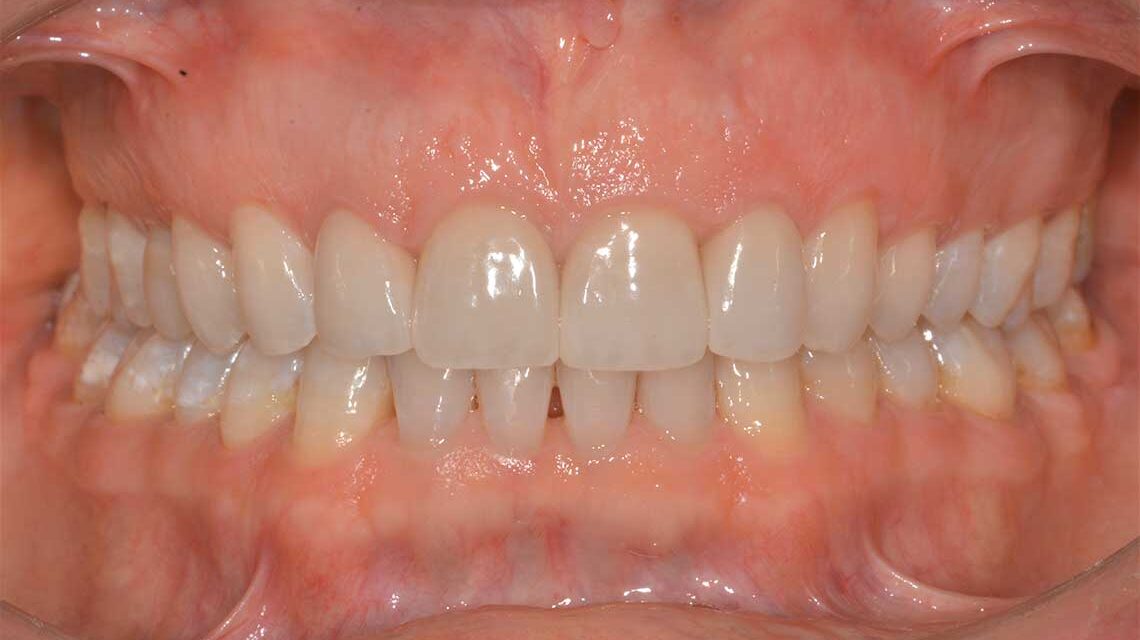

Ortodonzia allineatori – caso clinico 2